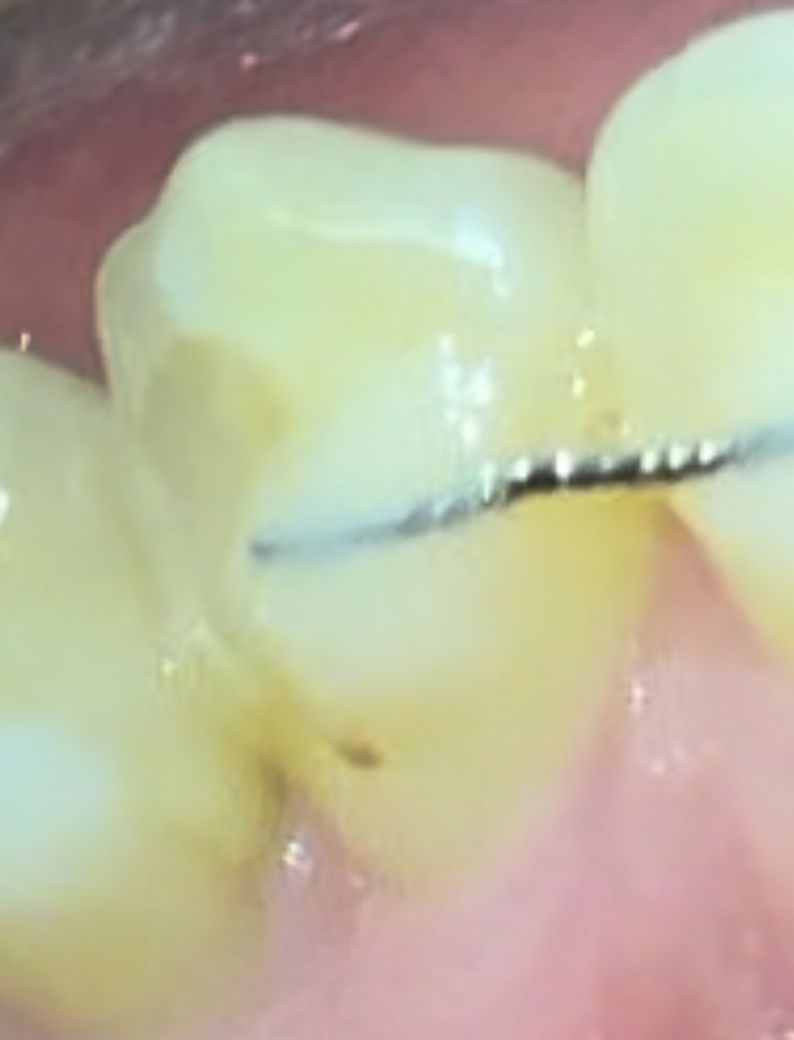

요 까만점 충치인가요? ㅠㅠ

시린건 없어요! 착색인지 충치인지 궁금해요

사진상으로는 애매하기는 하지만 착색일 가능성이 높아보입니다. 정확한 것은 치과 검진이 필요합니다.

사진에 보이는건 충치는 아니고 예전에 치료한부위에 착색이 된거 같습니다. 스켈링을 하면 제거가 될수 잇을것같습니다.

현재 교정유지장치 접착제부위에 착색이 된 것으로 보이며, 보다 정확한 상태 확인을 위해서는 치과 진료를 받길 권합니다.

위 사진상 충치라고 보여지지는 않고 유지장치를 붙여둔 레진 등의 색상이변색된 것 같습니다